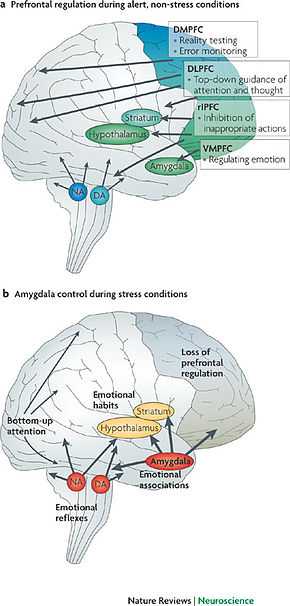

Depression has also shown 'unusual' activity in the amygdala (Figure 5), which is partly responsible for the processing and generation of emotions. Though it is not clear what the exact relationship is between the Amygdala and depression, current research suggests disruptive activity is present between the ventromedial prefrontal cortex (VMPFC), the right prefrontal cortex (PFC) and the Amygdala (See Figure 5).

The Amygdala is primarily responsible for the formation and processing of emotional reactions and emotional memories. Memories of emotional experiences imprint in the Amygdala's Neurons, creating emotional imprinting. Trauma causes a negative imprinting in the Amygdala's circuitry, meaning a fear response can be more easily triggered.

Stress & Stability

In times of non-stress, the VMPFC and the PFC regulate the emotional outputs streaming from the Amygdala. In times of stress, the emotional outputs override the regulation offered by the VMPFC and PFC. Raw emotions pour into the brain and consequently the emotional stability of the mind becomes unbalanced. This is also known as 'emotional flooding', and is a common characteristic of interpersonal stress. "Interaction between the Amygdala and the VMPFC may underlie the proper adaptation of levels of the stress hormone Cortisol on a daily basis." (ScienceDaily, 2007). Cortisol is... (http://news.bbc.co.uk/2/hi/health/7976489.stm). Stress is a trigger for emotional flooding and consequently instability to occur. It streams emotional outputs from the Amygdala which flood its regulators, the VMPFC and PFC cortexes.

The impact of stress also gives us insight into how other disorders destabilise emotions. The role of the VMPFC can be seen to regulate emotional outputs of the Amygdala When the outputs are too strong, the VMPFC becomes overwhelmed and is unable to efficiently regulate the streaming emotional outputs, meaning emotions begin to flood the brain. This theory can be applied to other disorders where 'emotional flooding' is common characteristic in response to a stressful stimuli. For example, anxiety, trauma and Post-traumatic Stress Disorder. Stress appears to be the trigger emotional imbalance in the brain.